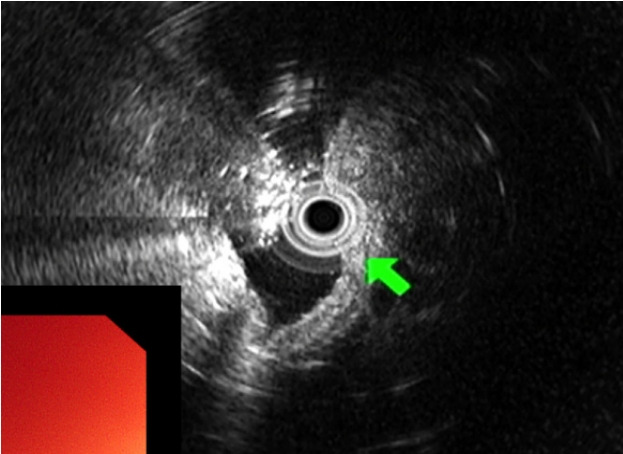

胃上皮下肿瘤(set)通常是无症状的,经常在内镜检查中偶然发现。胃内翻性增生性息肉(IHP)的特征是增生性粘膜向下生长到粘膜下层。由于这些特点,胃IHP经常被误诊为SET。胃ihp在大多数情况下是无症状的,是偶然发现的。值得注意的是,IHPs可能伴有腺癌或贫血,这是由于与这种病变相关的慢性出血;因此,建议内镜下粘膜下剥离术完全切除直径为bbbb2 cm的ihp。我们报告一个病例的胃IHP是在筛选内镜诊断在一个无症状的病人。我们观察到从SET中表达的白色化脓性渗出物,内窥镜超声检查显示SET起源于肌层粘膜。内镜下粘膜剥离术去除SET,最终组织病理学结果显示胃IHP。本病例报告强调,与白色渗出物相关的SET患者应怀疑ihp。

Gastric subepithelial tumors (SETs) are usually asymptomatic and are often detected incidentally during screening endoscopy. A gastric inverted hyperplastic polyp (IHP) is characterized by downward growth of hyperplastic mucosa into the submucosal layer. Owing to these characteristics, a gastric IHP is frequently misdiagnosed as a SET. Gastric IHPs are asymptomatic in most cases and are discovered incidentally. Notably, IHPs may be accompanied by an adenocarcinoma or anemia owing to chronic bleeding associated with this lesion; therefore, endoscopic submucosal dissection is recommended for complete excision of IHPs measuring > 2 cm. We report a case of gastric IHP that was diagnosed during screening endoscopy in an asymptomatic patient. We observed a whitish purulent exudate expressed from the SET, and endoscopic ultrasonography revealed a SET originating from the muscularis mucosa. Endoscopic submucosal dissection was performed to remove the SET, and final histopathological findings revealed a gastric IHP. This case report highlights that IHPs should be suspected in patients with a SET associated with whitish exudates.